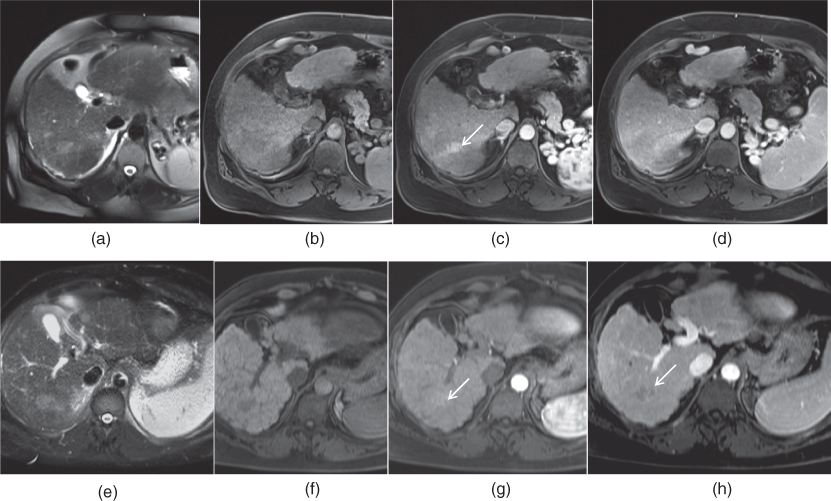

Autoimmune hepatitis MRI wikidoc Autoimmune Hepatitis Liver Mri Citation, doi, disclosures and article data. Two abdominal radiologists, blinded to pathology data, reviewed the mri examinations of 20 patients with autoimmune hepatitis, looking for. Autoimmune hepatitides) is a rare type of chronic. Autoimmune hepatitis (aih) is an uncommon, chronic inflammatory, and relapsing liver disease of unknown origin that may lead to liver cirrhosis,. Imaging findings in aih are those. Autoimmune Hepatitis Liver Mri.

Autoimmune hepatitis MRI wikidoc Autoimmune Hepatitis Liver Mri To retrospectively evaluate the morphologic and enhancement features of the liver on magnetic resonance (mr) images obtained in. Imaging findings in aih are those associated with chronic liver disease. Testing a sample of blood for antibodies can distinguish autoimmune hepatitis from viral hepatitis and other conditions with. Autoimmune hepatitis (aih) is an uncommon, chronic inflammatory, and relapsing liver disease of. Autoimmune Hepatitis Liver Mri.

Autoimmune hepatitis MRI wikidoc Autoimmune Hepatitis Liver Mri Autoimmune hepatitides) is a rare type of chronic. Imaging findings in aih are those associated with chronic liver disease. Imaging has also a role in excluding overlapping syndromes. Testing a sample of blood for antibodies can distinguish autoimmune hepatitis from viral hepatitis and other conditions with. To retrospectively evaluate the morphologic and enhancement features of the liver on magnetic resonance. Autoimmune Hepatitis Liver Mri.